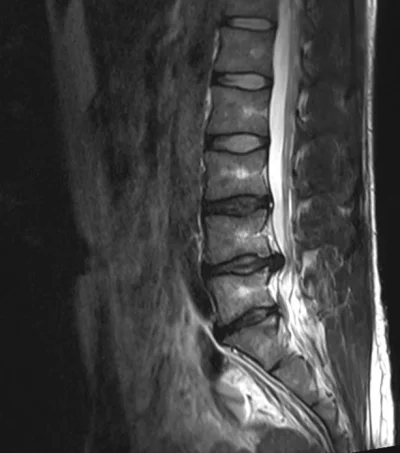

Kuin kaksi marjaa. Kuvien välissä yli 4 kk ja eteenpäin on menty...tai sitten ei. "Kyllä ne välilevynpullistumat itsestään kuivaa pois". "90% välilevynpullistumista paranee oireettomiksi 3 kk:ssa" :jahas: Sinällään jännä juttu että oireet ovat muuttuneet. Nyt en pysty enää istumaan hetkeäkään, mutta kävely onnistuu kivutta jos en istu.

Lekuri sanoi näiden viime kuvien jälkeen ettei kuvien perusteella mitään edistymistä/muutosta, mutta ei sitä kuvia leikata vaan oireita. On tosiaan jännä juttu miten kuvat on lähes identtiset 4 kk välillä, mutta nyt selkä on viikossa parantunut huomattavasti. Viime viikon maanantaina selkä oli kivuliain mitä se on koskaan aikaisemmin ollut. Makasin noroviruksen takia vessan lattialla yön yli ja seuraavana päivänä en pystynyt liikkumaan. Viikko sitten sattui niin saatanasti istua magneettikuvien jälkeen bussissa, mutta viikonloppuna kävin ensimmäistä kertaa tänä talvena lautailemassa. Itseasiassa kävin kahtena päivänä lautailemassa. Laskin lähes täydellä teholla, koska ajattelin ottaa komeasti viimeisen kerran kun olen laudan päällä. No, eipä tuo mennyt alkuunkaan huonommaksi.

Radiologin lausunnon mukaan siis prolapsi on kasvanut jonkun verran edelliseen kuvaan verrattuna ja sen takia paikat ovat voimaakkasti ahtautuneet. En todellakaan valita, mutta omituista kieltämättä että oireet ovat nyt helpottaneet. Jalkaa en pysty edelleenkään nostamaan aamulla kuin sen noin 30-40 cm ylöspäin. Iltapäivällä jalka heilahtaa kivutta 90-asteen kulmaan. Tunto on tallella, mutta akillesjänteen refleksi edelleen död ja tuskin enää palautuu koskaan. Mutta ei sillä mitään virkaa muutenkaan ole. Tästä on hyvä jatkaa kohti uusia loukkaantumisia :)